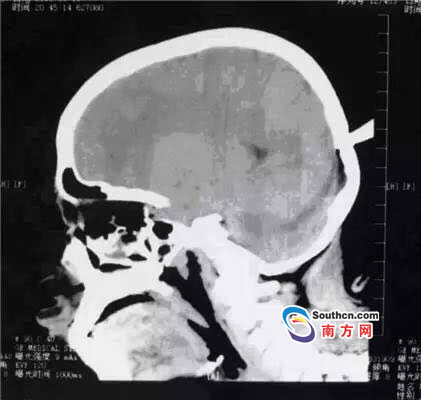

接到小玲受傷的消息,東莞市第三人民醫(yī)院急診科立即啟動(dòng)了急癥危重患者搶救流程。急癥頭部CT顯示,飛鏢已穿透小玲的顱骨,并突破硬腦膜,情況非常兇險(xiǎn),小玲命懸一線(xiàn)。